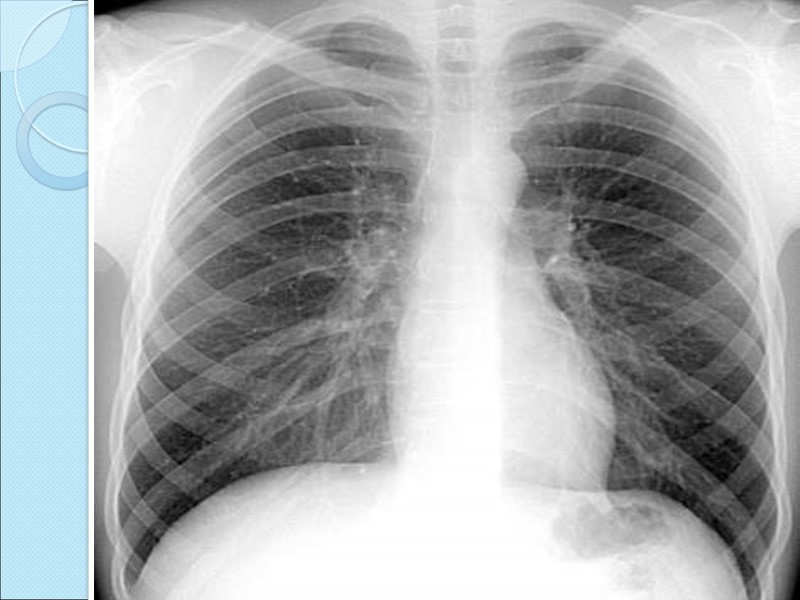

Рентген сәулесі біртекті емес ортадан өткенде, онда сәуленің жұтылуы да біртекті болмайды. Егер сәуленің таралу жолына флюоренсценттік экран қойса онда экранда бөгеттің пішініне сәйкес келетін жарықталу мен көлеңке көрінеді. Заттың құрлысын рентген сәулесімен зерттеудің негізі осы. Адам ағзасы рентген сәулесін түрліше жұтатын тіндер мен мүшелерден тұрады. Сондықтан рентген сәулесі адам ағзасынан өткенде түрліше жұтылып, экранда ішкі мүшелердің ақ-қара түсті бейнесін көруге болады

Егер адамның ағзасы қалыпты болса, онда өкпенің кескіні бірыңғай тегіс болады, ал патологиялық ауытқу болса (ісік, өкпе ауру, т.с.с.) онда өкпе кескіні шұбарланады. Сол кескін арқылы өкпенің физиологиялық күйін анықтауға болады. Адам ағзасының физиологиялық күйін анықтауды диагностика дейді.